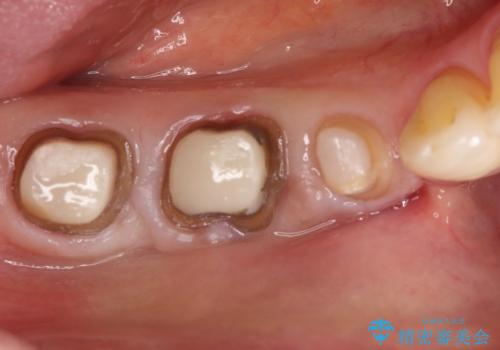

虫歯の治療 オールセラミッククラウン

- 他院にて以前治療した修復物の下に虫歯を認めたため、オールセラミックにて修復治療を行なっております。

オールセラミッククラウンは天然歯と同様に透明感を出すことができ、より審美的な治療が可能です。